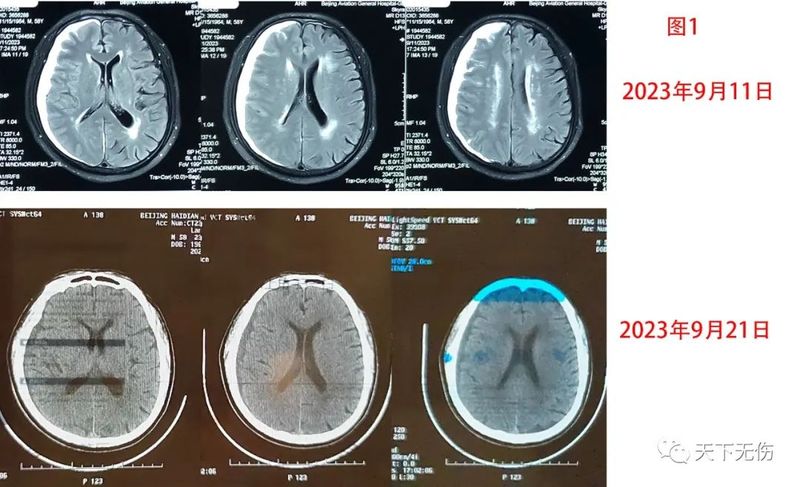

堅(jiān)持做硬膜下血腫研究